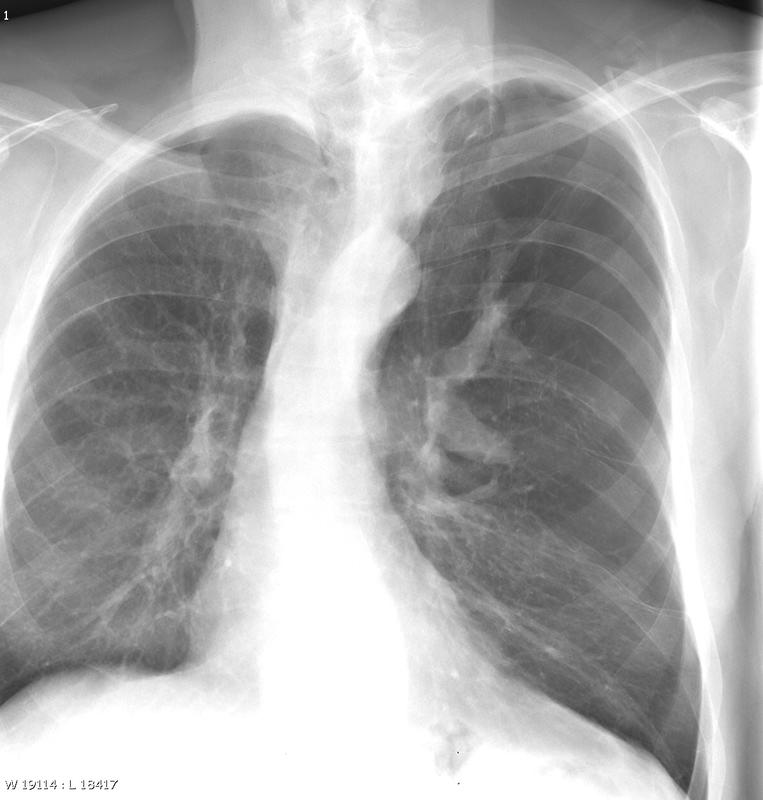

Gallery Congenital Bronchial atresia

Bronchial atresia